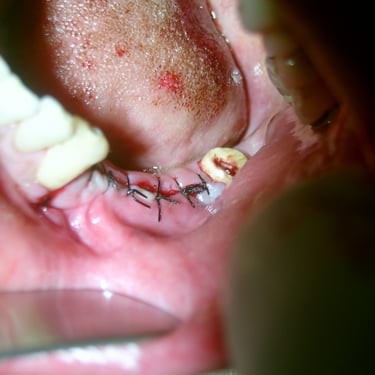

Oral and Maxillofacial Surgery

Extractions Frenectomy Flap surgery and bone grafting Wisdom teeth removal Surgical extractions Bone curettage Pericoronal flap removal